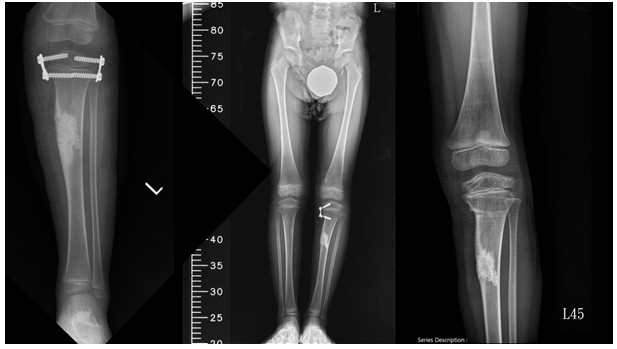

圖七為兒童骨科腫瘤團隊做腫瘤刮除、骨移植外,同時做生長抑制拉近雙腳長度(圖七中央),並於後續分次拔釘而有生長導引之效果,矯正患側脛骨關節面傾斜造成的膝外翻,最右側為最終矯正完成拔釘後之影像。

圖七